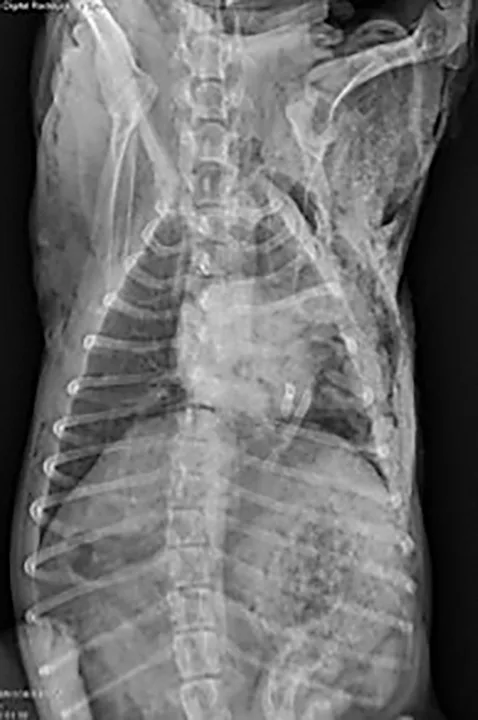

(A) Right lateral and (B) ventrodorsal radiographs of a 10-year-old neutered male schnauzer with flail chest from unknown trauma. The dog had severe subcutaneous emphysema, segmental fractions of the left 5th and 6th ribs, and a transverse fracture of the proximal left 7th rib. Left-sided pneumothorax and an alveolar pattern in the left cranial lung lobes were also noted.